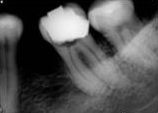

antes depois